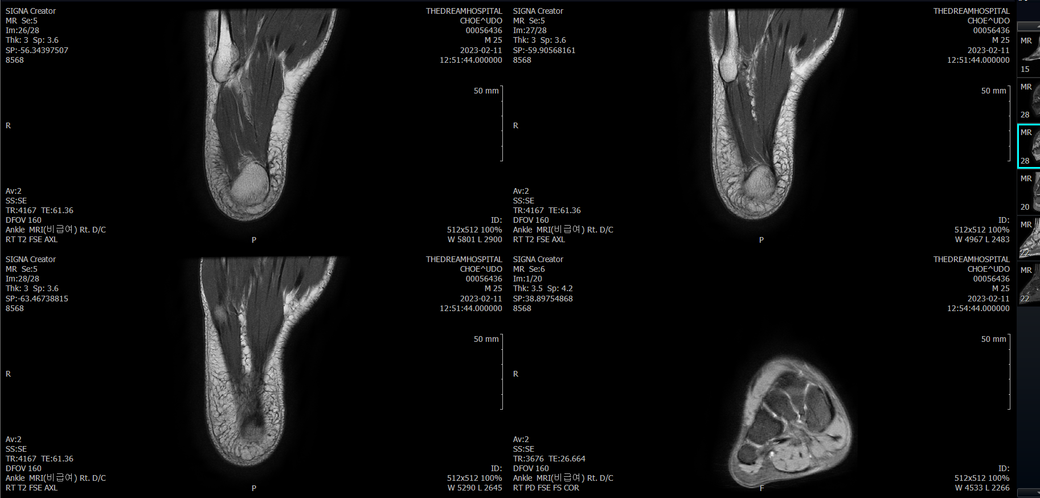

오른발목 mri 전체사진입니다. 제가 병원을 갈수없는상황인지라.... 봐주시면 감사하겠습니다.

엑스레이에서는 문제가 없다고 하여 오른발목 mri촬영했습니다.

우선 전반적으로 봤을 때 큰 이상은 없어보입니다.

전거비인대 등도 저명한 손상은 없는 것 같아 보이지만, 어느 부분의 통증 등으로 인해 촬영을 하셨는지 말씀을 해주신다면 보다 정확한 병변파악이 가능하겠으며, 병원에서 판독이 완료되신다면 전화 등으로 문의를 해보시는 것이 좋겠습니다.